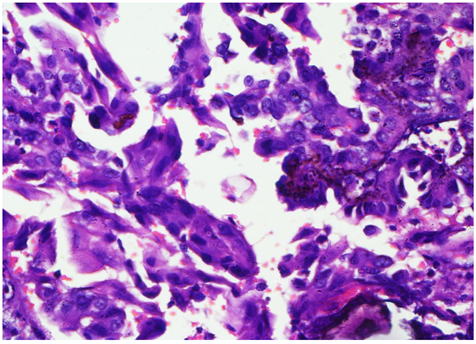

A 47 year old male came to the Surgical Clinics with complaints of progressively increasing midline neck swelling for the last 4 years. He had no history of pain, dysphasia, hoarseness of voice, fever, loss of appetite and loss of weight. He also had no history of any systemic illness and family history. On examination, a well-defined cystic, non tender, swelling, 8 cm×6 cm in size was seen in the mid of the neck. The overlying skin appeared to be normal with no signs of sinus or fistula. The mass was fixed to the underlying structures, was compressible, non-pulsatile, non-fluctuant and moving with deglutition. No neck nodes were palpable. A provisional diagnosis of a thyroglossal cyst was given. Fine needle aspiration cytology showed features of a cystic lesion. X‑ray chest was normal. On ultrasonography, a large lobulated cystic mass with hyper and hypoechoeic areas with focal calcification was seen. There was no abnormality detected in routine hematologic and urine investigations. Surgical excision of the cystic swelling with sistrunk’s procedure was performed. Grossly, the specimen was 10.4cm×6cm×3.8 cm in size, with multinodular and well capsulated external surface. Cut section showed a multiloculated cystic swelling with foci of solid grey white areas with focal papillary excrescences. Microscopic examination showed a multiloculated cystic lesion with variable sized thyroid follicular epithelial cells and foci of calcification. Focal areas of cellular atypia was noted within tumor cells exhibiting ground glass nuclei Figure 1 & 2. Immunohistochemical staining showed diffuse moderate intensity cytoplasmic positivity of Pan Cytokeratin Figure 3. A histopathologic impression of papillary carcinoma of thyroid in a thyroglossal cyst was made. Postoperative period was uneventful and our patient was absolutely all right. 50 Gy of Co-60 radiotherapy and adjuvant chemotherapy with Cisplatin 50mg/m2x6 cycles was administered. Our patient is doing well after 12 months of follow up.

Figure 2 Microscopic examination shows clusters of atypical thyroid follicular epithelial cells exhibiting ground glass nuclei and foci of calcification. Hematoxylin and Eosin x40X.